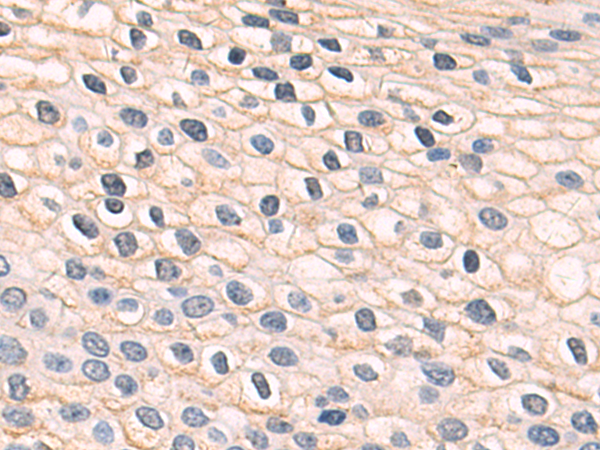

分类: 科研抗体货号: P06937别名: Ga55应用: IHC反应种属: Human, Mouse